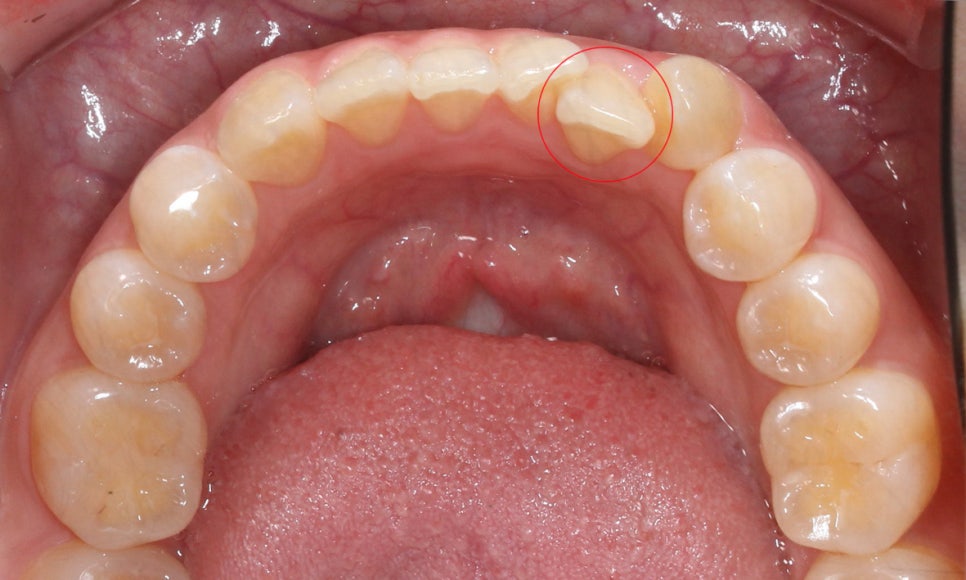

상악의 경우 교합면을 보시면

중절치의 뻐드러짐으로 인해

안모의 형태가 삐뚤어진 모습을 확인할 수 있습니다.

2D교정을 시작하시면 위와 같이 치아의 안쪽면에

브라켓이 부착되기 때문에 겉으로 보여지는 부분은

내 치아 그대로 자연스러운 교정이 가능합니다.

구치부에는 브라켓이 부착되지 않습니다.